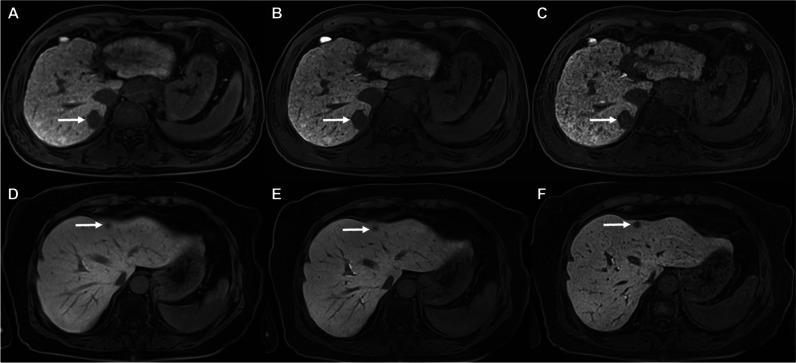

To investigate whether a deep learning (DL) controlled aliasing in parallel imaging results in higher acceleration (CAIPIRINHA)-volumetric interpolated breath-hold examination (VIBE) technique can improve image quality, lesion conspicuity, and lesion detection compared to a standard CAIPIRINHA-VIBE technique in gadoxetic acid-enhanced liver MRI.

This retrospective single-center study included 168 patients who underwent gadoxetic acid-enhanced liver MRI at 3 T using both standard CAIPIRINHA-VIBE and DL CAIPIRINHA-VIBE techniques on pre-contrast and hepatobiliary phase (HBP) images. Additionally, high-resolution (HR) DL CAIPIRINHA-VIBE was obtained with 1-mm slice thickness on the HBP. Three abdominal radiologists independently assessed the image quality and lesion conspicuity of pre-contrast and HBP images. Statistical analyses involved the Wilcoxon signed-rank test for image quality assessment and the generalized estimation equation for lesion conspicuity and detection evaluation.

DL and HR-DL CAIPIRINHA-VIBE demonstrated significantly improved overall image quality and reduced artifacts on pre-contrast and HBP images compared to standard CAIPIRINHA-VIBE (p < 0.001), with a shorter acquisition time (DL vs standard, 11 s vs 17 s). However, the former presented a more synthetic appearance (both p < 0.05). HR-DL CAIPIRINHA-VIBE showed superior lesion conspicuity to standard and DL CAIPIRINHA-VIBE on HBP images (p < 0.001). Moreover, HR-DL CAIPIRINHA-VIBE exhibited a significantly higher detection rate of small (< 2 cm) solid focal liver lesions (FLLs) on HBP images compared to standard CAIPIRINHA-VIBE (92.5% vs 87.4%; odds ratio = 1.83; p = 0.036).

DL and HR-DL CAIPIRINHA-VIBE achieved superior image quality compared to standard CAIPIRINHA-VIBE. Additionally, HR-DL CAIPIRINHA-VIBE improved the lesion conspicuity and detection of small solid FLLs. DL and HR-DL CAIPIRINHA-VIBE hold the potential clinical utility for gadoxetic acid-enhanced liver MRI.

与标准 CAIPIRINHA-VIBE 相比,DL 和 HR-DL CAIPIRINHA-VIBE 在平扫和 HBP 图像上均显著提高了整体图像质量,减少了伪影(p<0.001),同时采集时间更短(DL 比标准,11s 比 17s)。然而,前者的外观更具合成感(均 p<0.05)。在 HBP 图像上,HR-DL CAIPIRINHA-VIBE 比标准和 DL CAIPIRINHA-VIBE 具有更高的病灶显著性(p<0.001)。此外,在 HBP 图像上,HR-DL CAIPIRINHA-VIBE 检测到的小(<2cm)实性局灶性肝脏病变(FLL)的检出率显著高于标准 CAIPIRINHA-VIBE(92.5%比 87.4%;比值比=1.83;p=0.036)。

与标准 CAIPIRINHA-VIBE 相比,DL 和 HR-DL CAIPIRINHA-VIBE 获得了更好的图像质量。此外,HR-DL CAIPIRINHA-VIBE 提高了小的实性 FLL 的病灶显著性和检出率。DL 和 HR-DL CAIPIRINHA-VIBE 在钆塞酸增强肝脏 MRI 中具有潜在的临床应用价值。